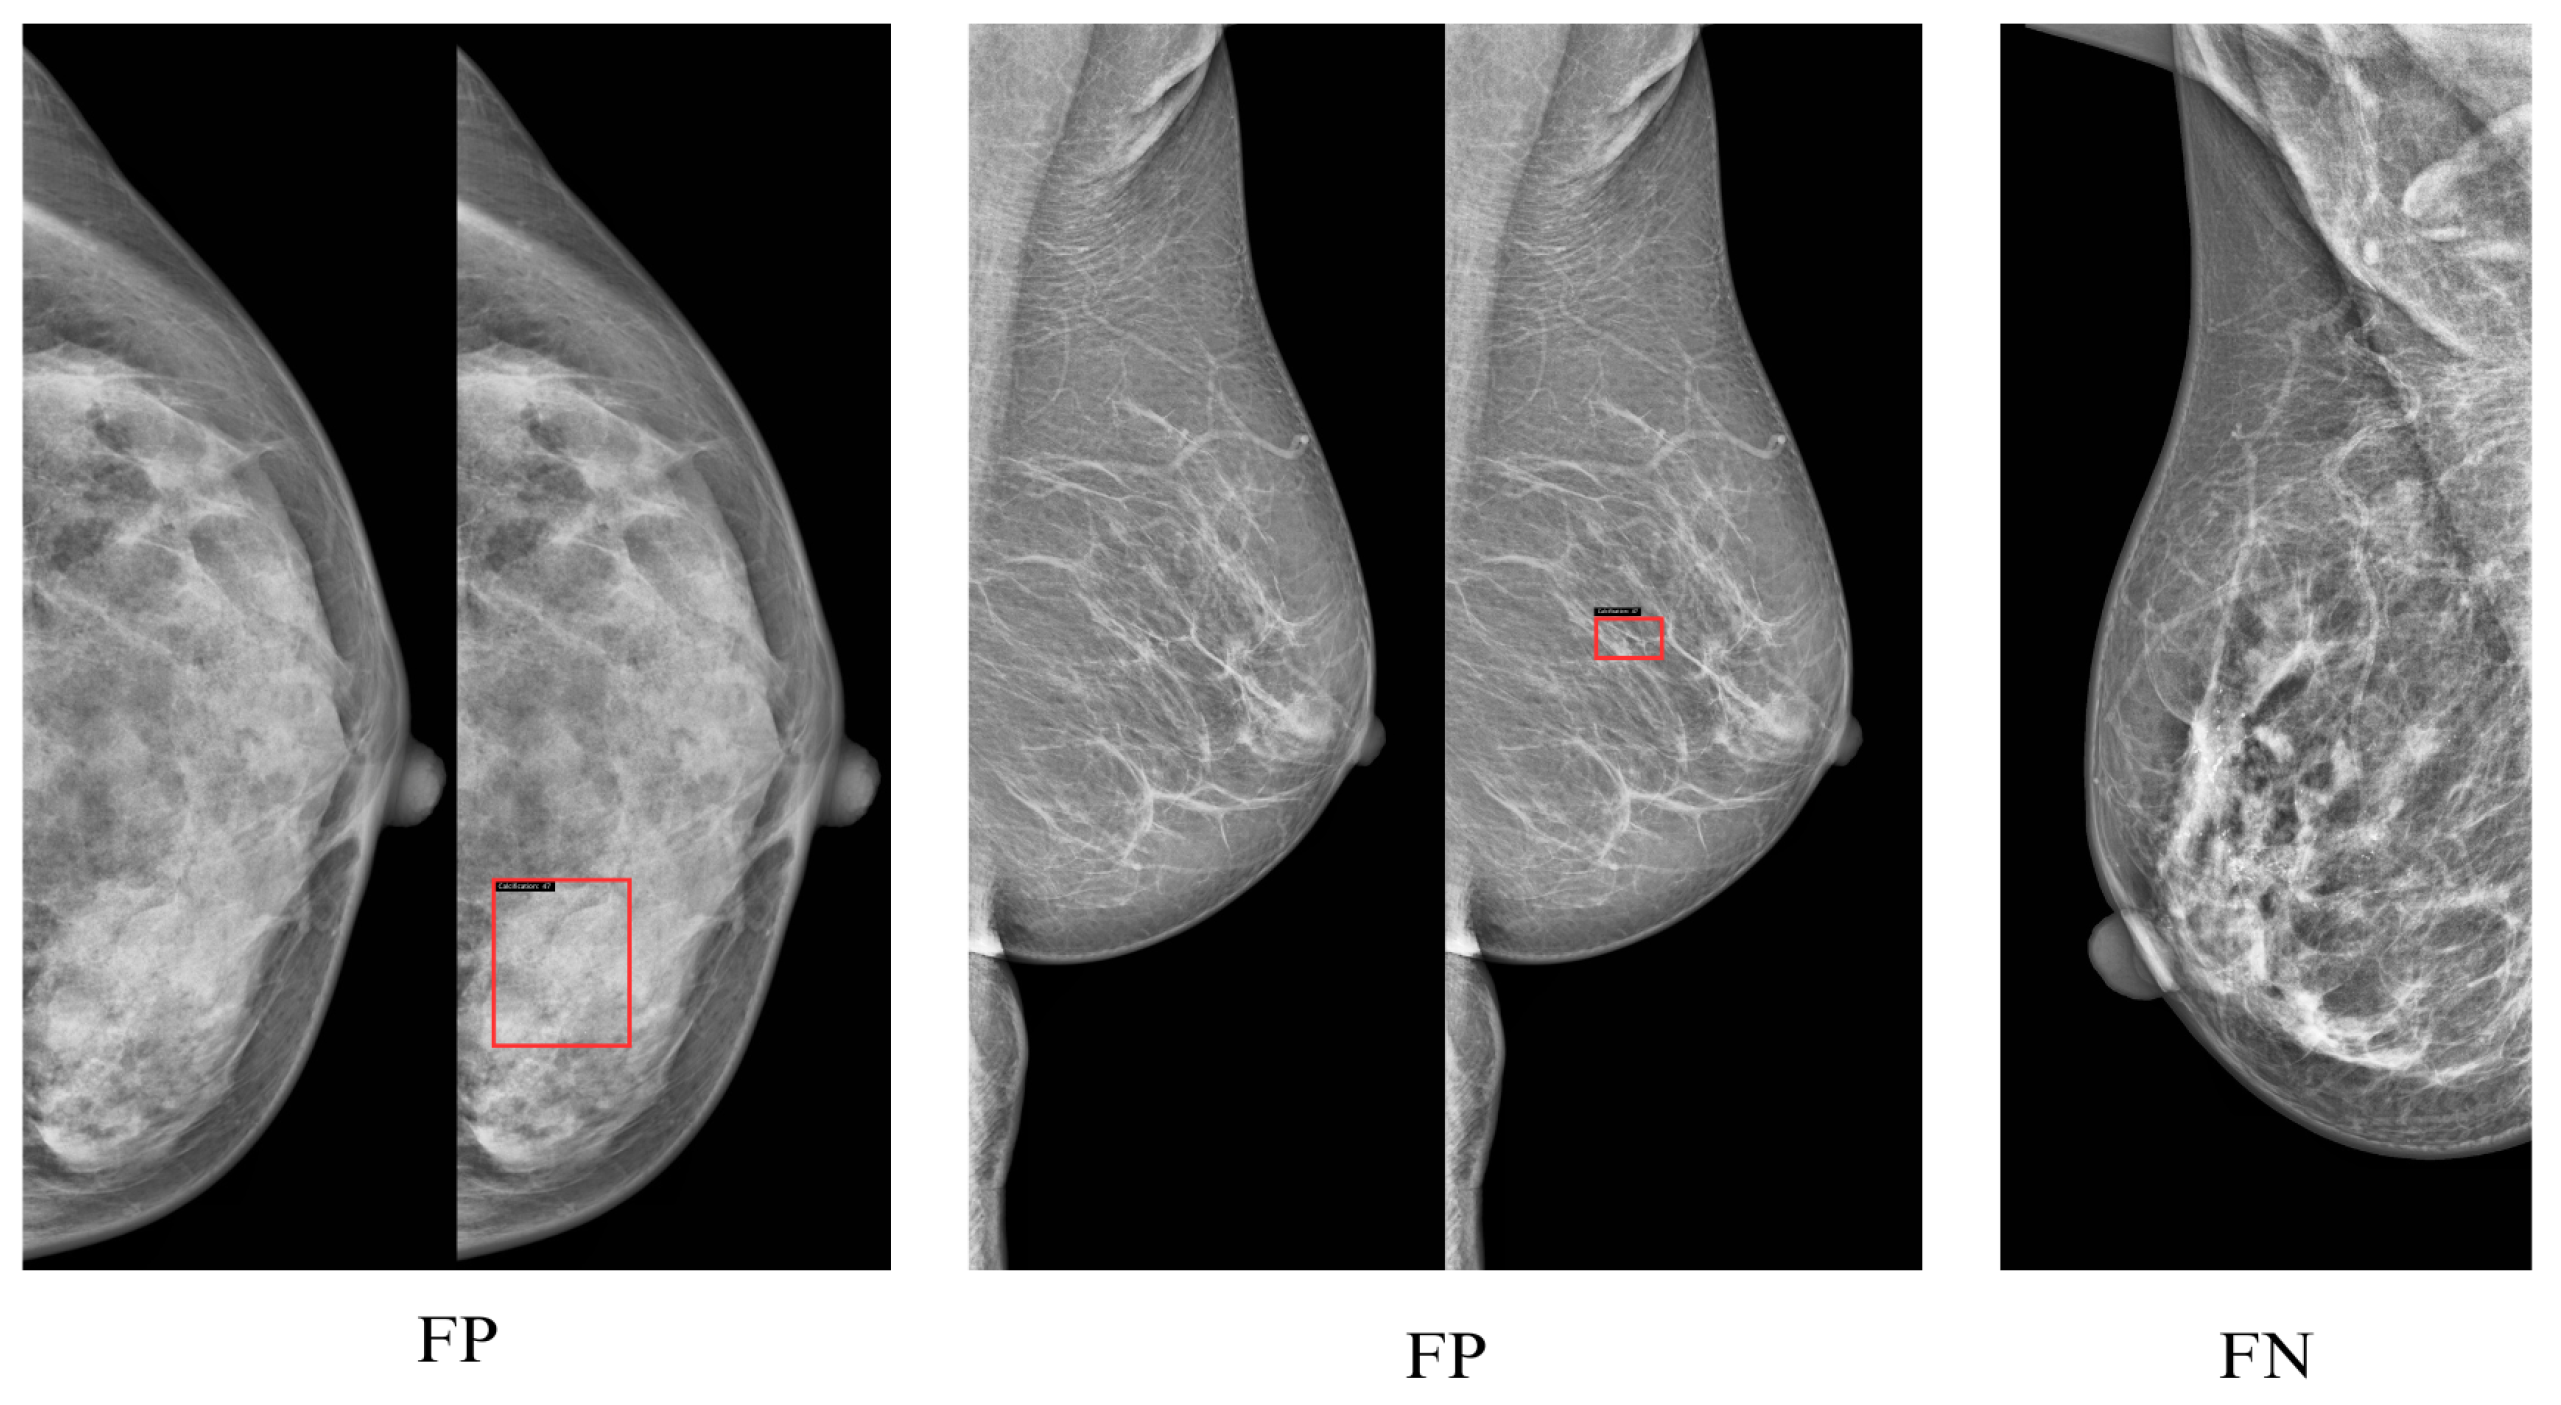

Visualization of Model Performance